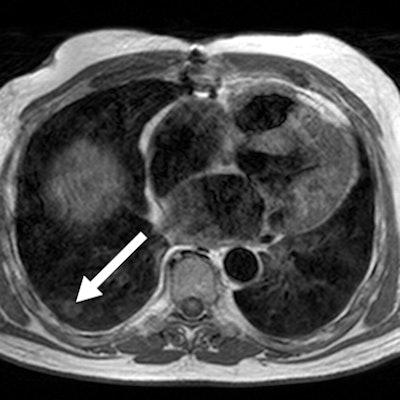

![]() |

| Axial T1-weighted image shows right lower lobe lung nodule (arrow) in 67-year-old man referred for evaluation of left ventricular function and myocardial viability. |